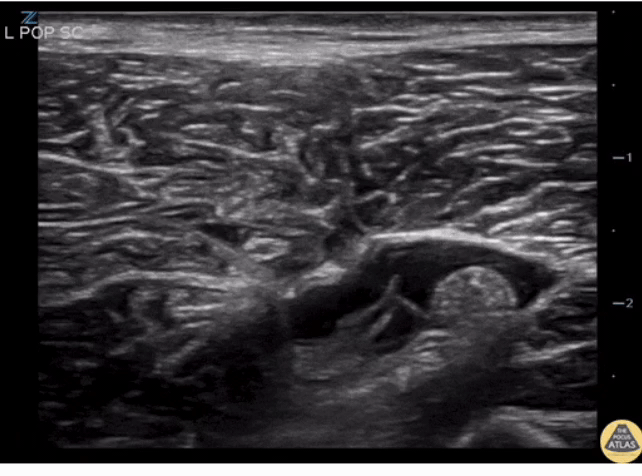

Visualizing and blocking the TN and CPN:

How do you know you’re in the right place?

• The anesthetic spreads proximally and distally to the site of the injection around both divisions of the nerve, or the spread of the local anesthetic within the sheath proximal to the site of injection.

• A single injection of local anesthetic typically suffices, typically 15-30cc of 0.5% ropivicaine.